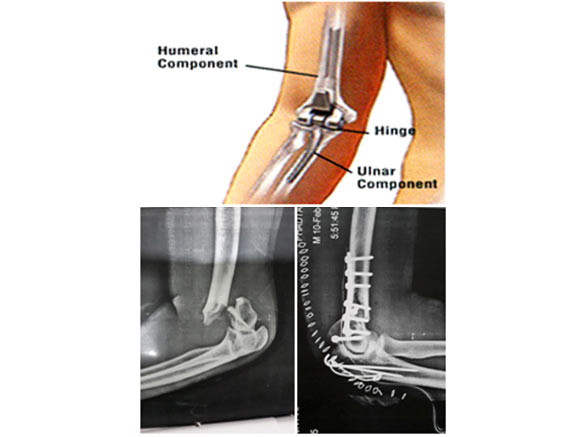

Elbow Replacement

Elbow replacement surgery involves replacing the damaged elbow joint with artificial components known as prosthetics.

The artificial joint consists of metal stems connected by a hinge that allows bending and movement similar to the natural elbow joint.